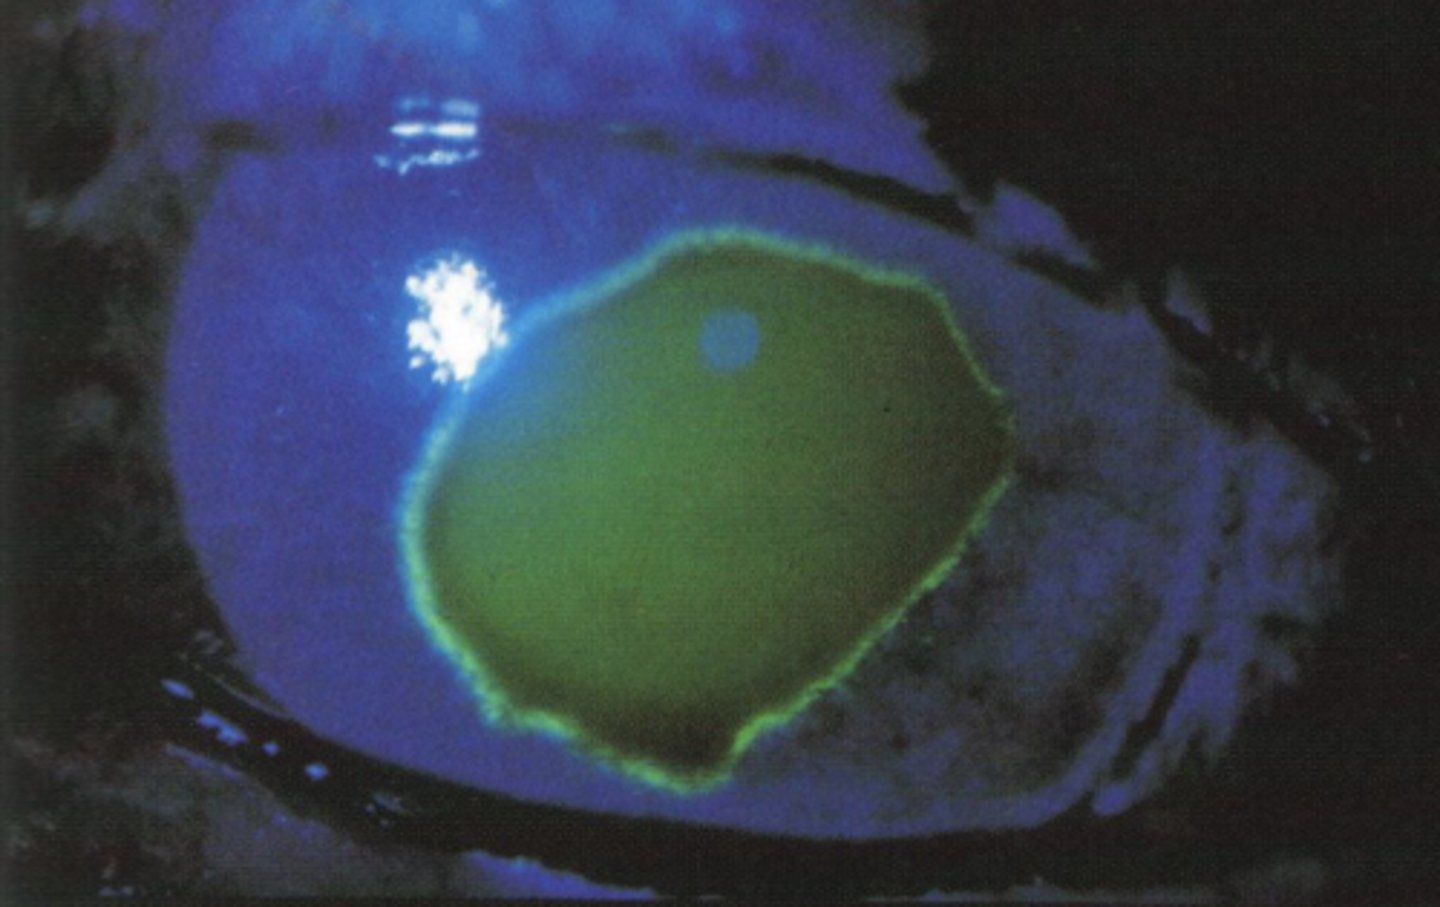

image - corneal abrasion